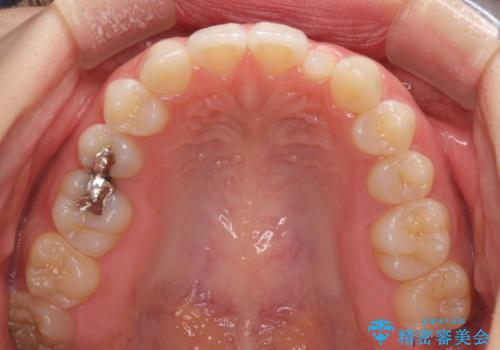

海外転居前に気になる前歯を整えたい 上下前歯の部分矯正

- 1年後に海外に転居するため、気になる前歯を矯正治療で整えたいとのことで来院された患者様です。

下顎は叢生が強かったため、奥歯までワイヤーを装着し、上顎は前歯の一部のみ気になっていたので、その部分にだけワイヤー装置を装着することとしました。